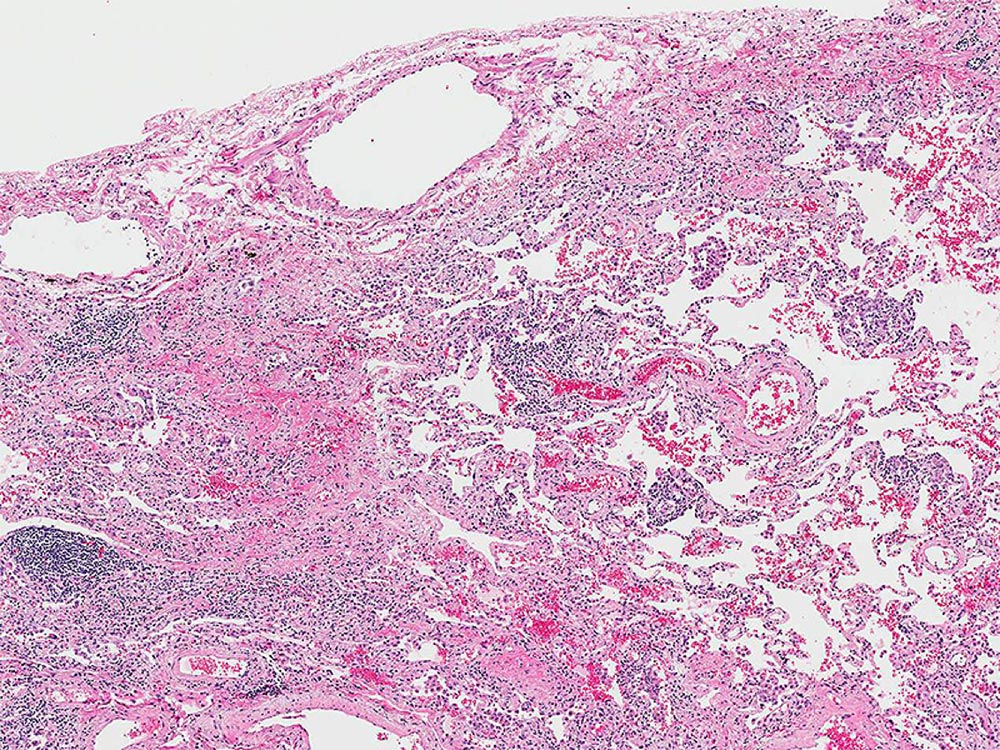

Low magnification photomicrograph illustrating prominent inflammation and airway-centered fibrosis in a patient with hypersensitivity pneumonitis.

Image courtesy of and used with permission from Kirk Jones, MD.